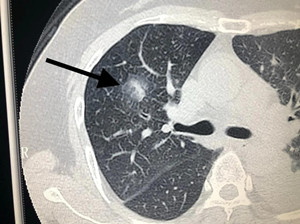

指病灶内实性成分直径大于5mm的mGGN;病灶直径大于10mm的pGGN;具有分叶征、毛糙边缘、毛刺征、空泡征、胸膜凹陷征等恶性征象的GGN;任意大小的pGGN或内部实性成分直径小于5mm的mGGN,若随访过程中出现病灶增大或密度增高;结节出现任何其他浸润性病灶特征。